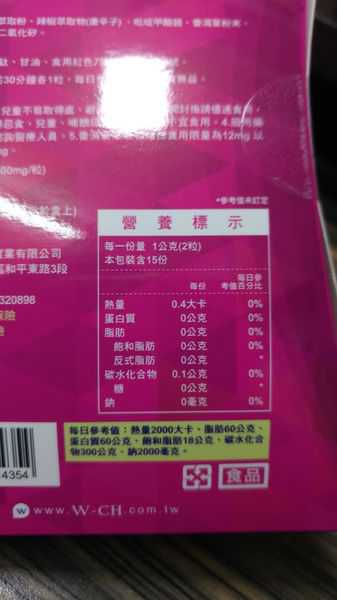

Supercut塑魔纖立塑膠囊的成分有:瓜拿那萃取粉、肉桂萃取粉、辣椒萃取物(唐辛子)、吡啶甲酸鉻、番瀉葉粉末、玉米澱粉、氧化鎂、二氧化矽。

番瀉葉萃取物每日食用限量為12mg以下,